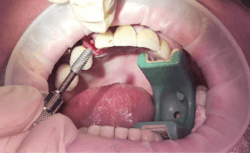

Another reason immediate placement is advantageous is that once the extraction is complete, the hole is usually already in the proper place for the implant. You may have to redirect your osteotomy slightly palatally, mesially, or distally, but the socket serves as an excellent guide for placement. In some cases, especially premolars, you can use an implant with aggressive threads to place without any osteotomy at all. You can engage the mesial and distal walls to achieve primary stability. This greatly shortens the appointment time, lowers risk, and increases patient satisfaction. Figures 1 and 2 show a MorsTorq in site No. 21 that was placed after an atraumatic extraction during my most recent two-day Louisiana Implant Institute course. Note the sharp threading on the MorsTorq, which allows for optimized immediate placement performance.There are some circumstances where immediate placement is not desirable. If the socket is too large to engage the mesial and distal walls and vital anatomical structures are located just apical to the socket, immediate placement is not recommended. Chronically infected sites also present a higher risk for immediate placement. If you can completely rid the socket of all soft tissue and the patient has the appropriate antibiotics onboard, it is possible. However, most of these cases are more predictably treated with early placement (waiting four to six weeks without grafting) or delayed placement (three to six months with grafting).